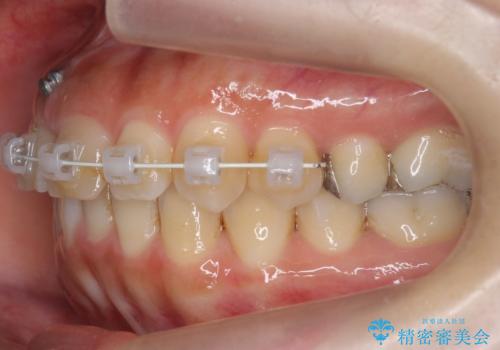

前歯のがたつき ガミースマイルの改善

- 前歯のがたつきとガミースマイルの改善を希望して来院。

ガミーは非常に軽度でひどくはなかったのですが、改善を強く希望されていました。

上の前歯をひっぱりあげて目立たなくするために、上の前歯のワイヤー部分矯正を行い、ミニスクリューからわずかに引っ張り上げました。

また、右上の犬歯の反対咬合についてもワイヤー矯正で短期間で改善することができました。

前歯の過蓋咬合についても改善しています。